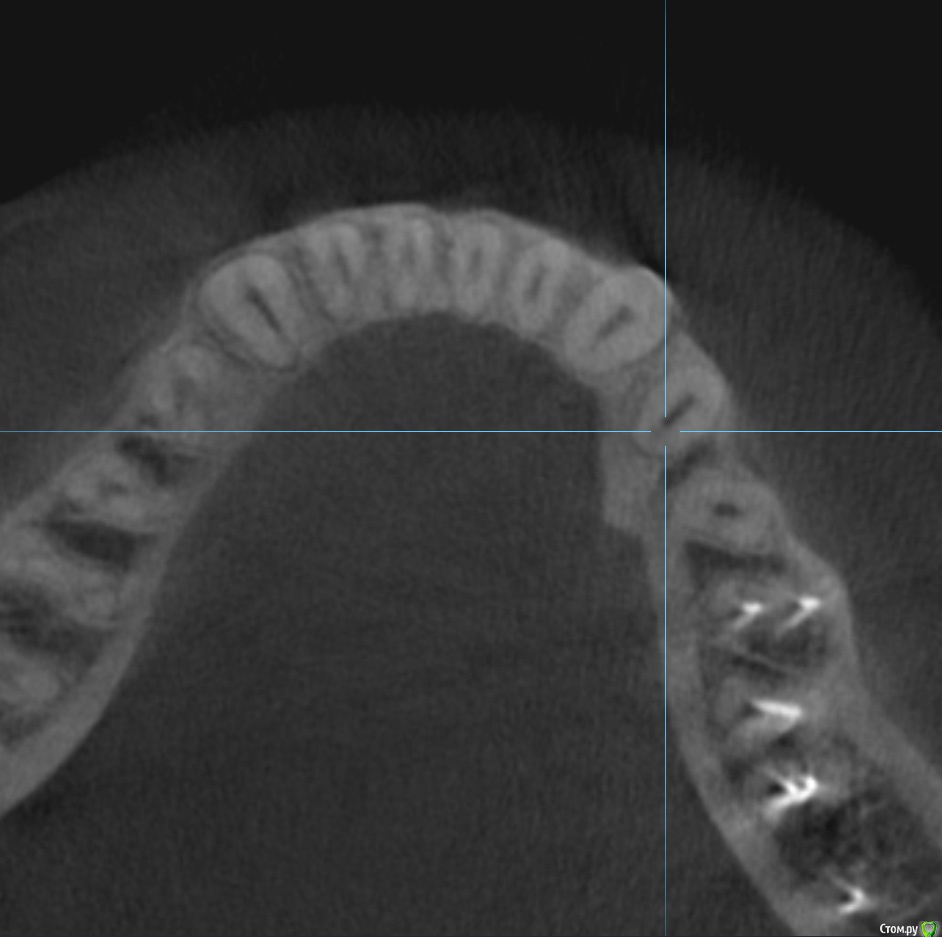

Tot20 Опубликовано 23 августа, 2019 Поделиться Опубликовано 23 августа, 2019 (изменено) Здравствуйте, мне нужен ваш совет. На фото моя проблема. Это видимо какой-то костный нарост. Так мне сказали пару лет назад после того как я делал кт. Он не болит. На ощупь твёрдый.Зубы рядом - живые, зубы не болят. Сейчас этот нарост стал крупнее, раньше он был поменьше. А впервые его я заметил лет 5-7 назад. Что это? Как оно называется в медицинской терминологии? Стоит ли беспокоится? Изменено 23 августа, 2019 пользователем Tot20 Ссылка на комментарий

Tot20 Опубликовано 23 августа, 2019 Автор Поделиться Опубликовано 23 августа, 2019 (изменено) Фото Изменено 23 августа, 2019 пользователем Tot20 Ссылка на комментарий